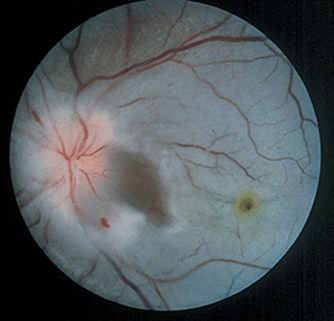

FIGURE 21-4

Retinal vasculitis, uveitis, and hemorrhage in a 32-year-old woman with Crohn’s disease. Note that the veins are frosted with a white exudate. Visual acuity improved from 20/400 to 20/20 after treatment with intravenous methylprednisolone.